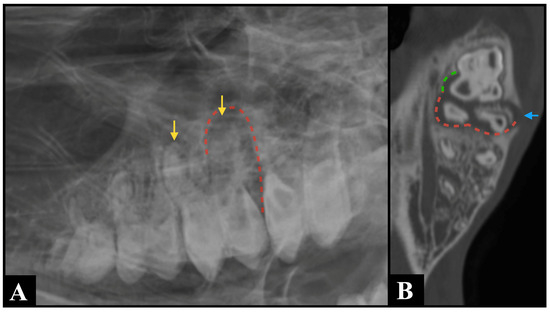

Figure 3.

An R30° D-LVO radiographic projection (A) identified shortening and blunting of the root of Triadan 210 (yellow arrows), along with widening of the periodontal ligament space (red dotted line) surrounding its distal roots, which are findings consistent with a suspected periapical infection. Bone window computed tomography multiplanar reconstructed image ((B), dorsal plane) confirmed the suspected findings (red dotted line) and provided additional information, demonstrating involvement of Triadan 211, where the mesiopalatal root exhibited widening of the periodontal ligament space (green dotted line) and an associated complete interruption of the alveolar bone (blue arrow).